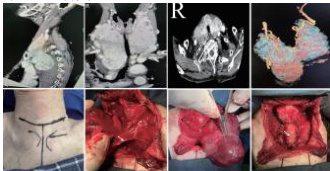

图1:甲状腺CT 平扫,A 矢状位,B 冠状位,C 轴位,显示巨大颈胸骨后甲状腺肿,肿物部分突入胸骨后并气管受压变窄;D 甲状腺CT 三维重建,显示巨大甲状腺肿及主要血供来源;E 术前颈部未触及明显包块,做低位领口切口;F 术中解剖暴露左侧喉返神经,G 术中解剖暴露右侧喉返神经及上提的纵膈内甲状腺组织,H 切除全部甲状腺后暴露气管无塌陷

大量的临床实践证明,绝大多数(超过 90%) )的胸骨后甲状腺肿,即使体积巨大、下极深入主动脉弓水平甚至后纵隔,其主要血供仍来源于颈部的甲状腺上、下动脉。这一核心解剖学特征为经颈部入路切除肿瘤提供了理论基础。在一项涵盖31 例巨大颈胸骨后甲状腺肿(肿瘤最大直径均超过 10cm)的研究中,所有患者均通过颈部低位弧形切口成功完整切除肿瘤,无一例需中转开胸。其关键手术技巧在于:首先于颈部充分暴露并控制甲状腺的主要血管,通过逐步结扎和离断甲状腺上、下动脉及甲状腺中静脉,有效阻断肿瘤血供;随后,可根据情况切断甲状腺峡部,增加两侧腺叶的活动度;最后,术者应紧贴肿瘤包膜进行锐性分离,避免盲目使用手指钝性剥离,以防撕裂纵隔内脆弱的静脉丛而导致难以控制的大出血,在直视下将肿瘤逐步、轻柔地由胸廓入口完整提拉至颈部切口并切除。这一策略的成功实施,标志着甲状腺外科在处理复杂病例时,已从依赖扩大手术路径转向依靠精细解剖技巧的理念转变。